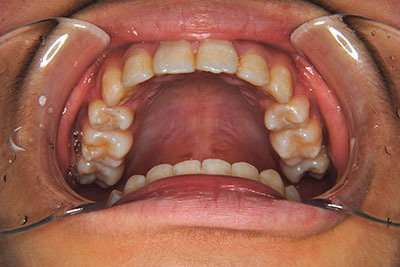

歯が乳歯から永久歯に生え変わった小学生高学年や、中高生でも矯正治療に手遅れということは全くありません。

成長中の顎の骨を矯正できたり、この時期の矯正はおとなになってから矯正治療を始めるよりも短期間で済むことがほとんどです。当院だとおおよそ1年で動的治療(マルチブラケット装置をつける期間)が終わることが多いです。